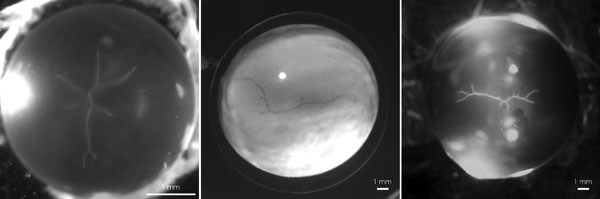

Figure 15. Compromised sutural anatomy following experimental pathologies

Abnormal sutures typical of lenses from animals with diabetes induced by streptozotocin injection (left), after vitrectomy (middle), and trabeculectomy (right). The abnormal suture branches are generally localized at regions of suture branches defined by key fibers (the peripheral and distal origins and midpoint of suture branches).